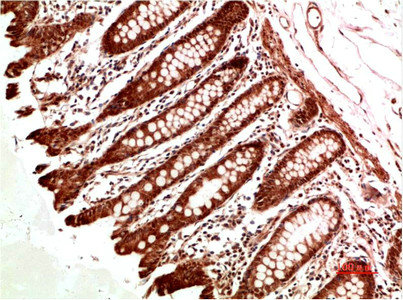

Immunohistochemical analysis of paraffin-embedded Human Colon Carcinoma Tissue using ATM Rabbit pAb diluted at 1:500.